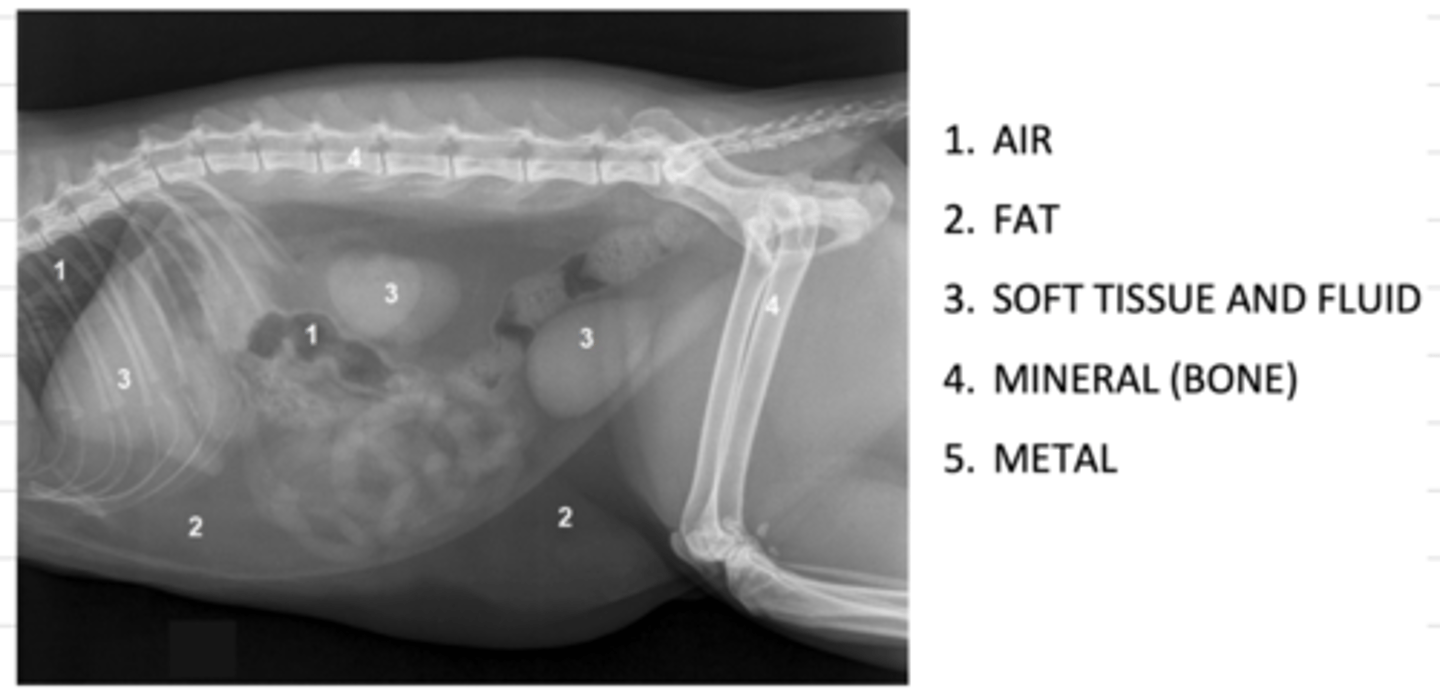

what are the 5 opacities of a radiograph, from most radioluscent to most radiopaque?

1. air

2. fat

3. soft tissue and fluid

4. mineral (bone)

5. metal

what are the 5 opacities of a radiograph?